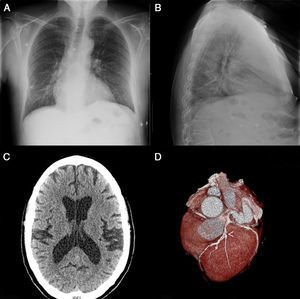

El electrocardiograma al ingreso presentaba ritmo sinusal con supradesnivel del ST de 2mm en V1-V3 y onda T isodifásica en I y aVL con tendencia, en electrocardiogramas posteriores, a la normalización del supradesnivel anterior, aunque con persistencia de ondasT negativas en precordiales (fig. 1). La radiografía de tórax, por su parte, evidenció un infiltrado basal derecho (fig. 2A,B) en el posible contexto de broncoaspiración, mientras que la tomografía computarizada (TC) cerebral mostró prominencia de los surcos y cisuras cerebrales con dilatación del sistema ventricular en relación con atrofia cerebral corticosubcortical. No se identificaron signos de hemorragia intra ni extraaxial, ni signos de expansividad que sugiriesen la existencia de una lesión ocupante de espacio ni signos de isquemia cerebral aguda (fig. 2C).

La radiografía de tórax en posteroanterior (A) y lateral (B) evidencia infiltrado a nivel basal del pulmón derecho. La tomografía computarizada (TC) cerebral (C) muestra prominencia de los surcos y cisuras cerebrales con dilatación del sistema ventricular. La angio-TC de arterias coronarias (D) muestra enfermedad significativa a nivel de la descendente anterior (punta de flecha) y de la circunfleja.

La ecocardiografía transtorácica de control evidenció hipertrofia concéntrica ligera del ventrículo izquierdo con función global conservada (fracción de eyección por Simpson del 59%) sin trastornos segmentarios de la contractilidad. No se evidenció derrame pericárdico ni alteraciones a nivel valvular ni de la función del ventrículo derecho. Por su parte, la angio-TC de arterias coronarias mostró hallazgos compatibles con enfermedad significativa de 3vasos (fig. 2D).